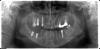

kmatv Опубликовано 13 августа, 2012 Поделиться Опубликовано 13 августа, 2012 А вот такая картинка получается после расщепления гребя толщиной 3мм. Обнаружил после того как надо было доставить 12з в тонкий гребень, открылся и увидел. на 12з сделал минислпит, 13 закрыл костным блочком. Контрольного КТ не делал пока ибо не было жалоб. После протезирования зондироваласть плотная субстанция под десной 13з. Наблюдаю Ссылка на комментарий

kmatv Опубликовано 13 августа, 2012 Поделиться Опубликовано 13 августа, 2012 Агрессивный сплит получился, все было заполнено биоссом, правда без мембран. Ссылка на комментарий

kmatv Опубликовано 13 августа, 2012 Поделиться Опубликовано 13 августа, 2012 (изменено) по поводу Nobel я Вас понял орто через 2 мес- нет резорбции. Изменено 13 августа, 2012 пользователем kmatv Ссылка на комментарий

kmatv Опубликовано 13 августа, 2012 Поделиться Опубликовано 13 августа, 2012 я про этот случай, фотообман или они вровень, или Вы потом их дозакрутили?Что значит фотообман? Думаю что на уровне, но густо обсыпаны биоссом. Ссылка на комментарий